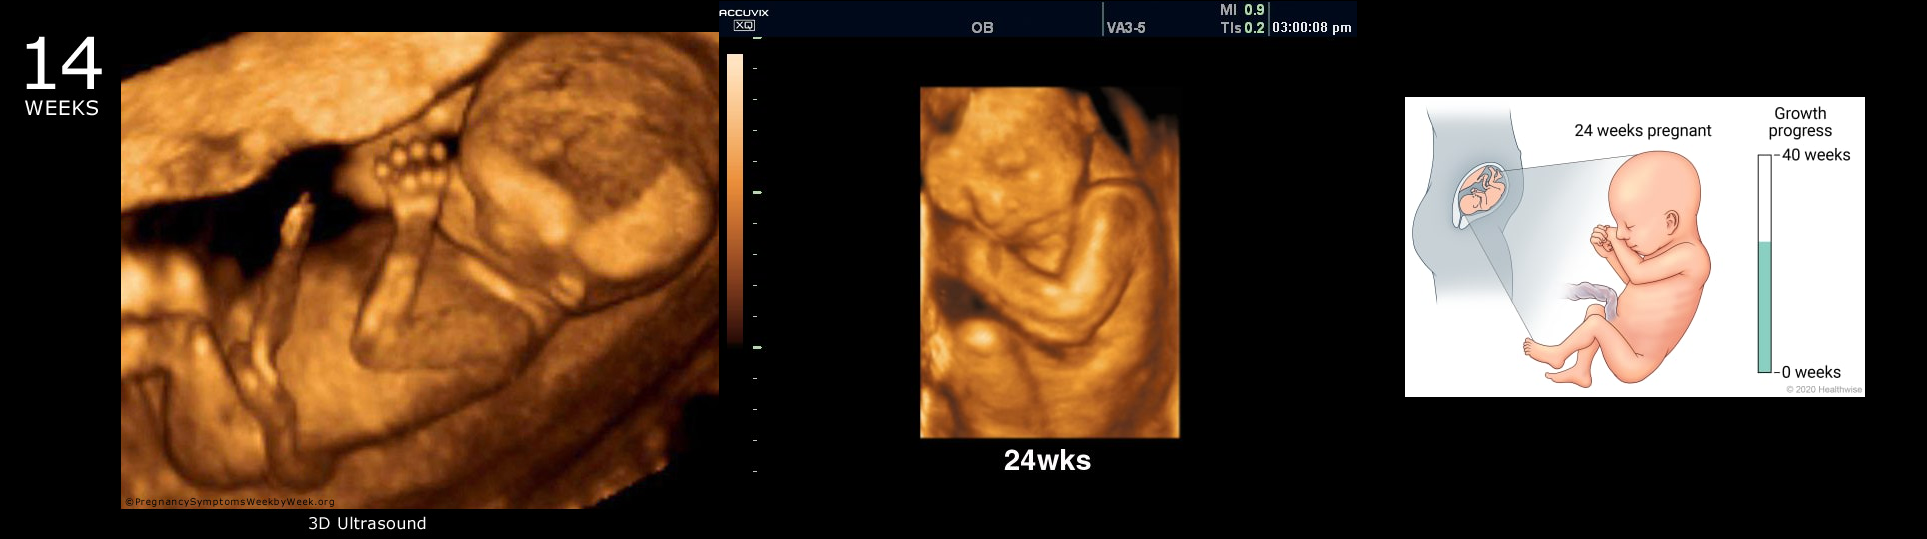

File: pregnancy.png (1.07 MB, 1927x539)

Look at picrelated, that's respective a 14 and 24 weeks baby, they have hands, a face, nose, and above all else, their own UNIQUE DNA, and when a person chooses to abort, they choose to DISMEMBER that baby while he is ALIVE. No, you grow the fuck up, you fucking imbecile excuse of human being, waste of space. Do you think that advocating for the killing of babies on the internet is funny?